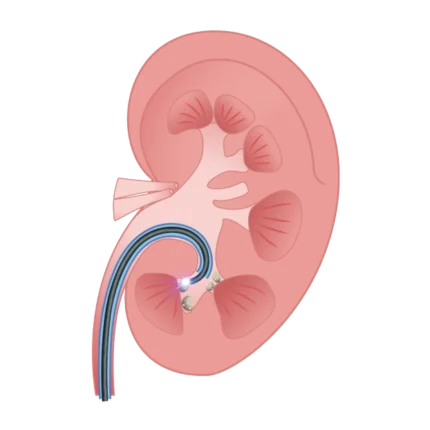

Cistoscopio digital flexible de un solo uso BubbleView serie C

Visibilidad inigualable: resolución de megapíxeles, campo de visión de 140°, profundidad de campo de 3–100 mm, excelente campo quirúrgico.

Inserción más suave: diseño preciso Easetip con punta distal en forma de bala y tubo de inserción con rigidez segmentada.

Maniobrabilidad mejorada: diámetro del tubo de inserción de 4.8 mm, canal de instrumentos de 2.2 mm de ancho, rango de angulación de 235° hacia arriba / 145° hacia abajo.